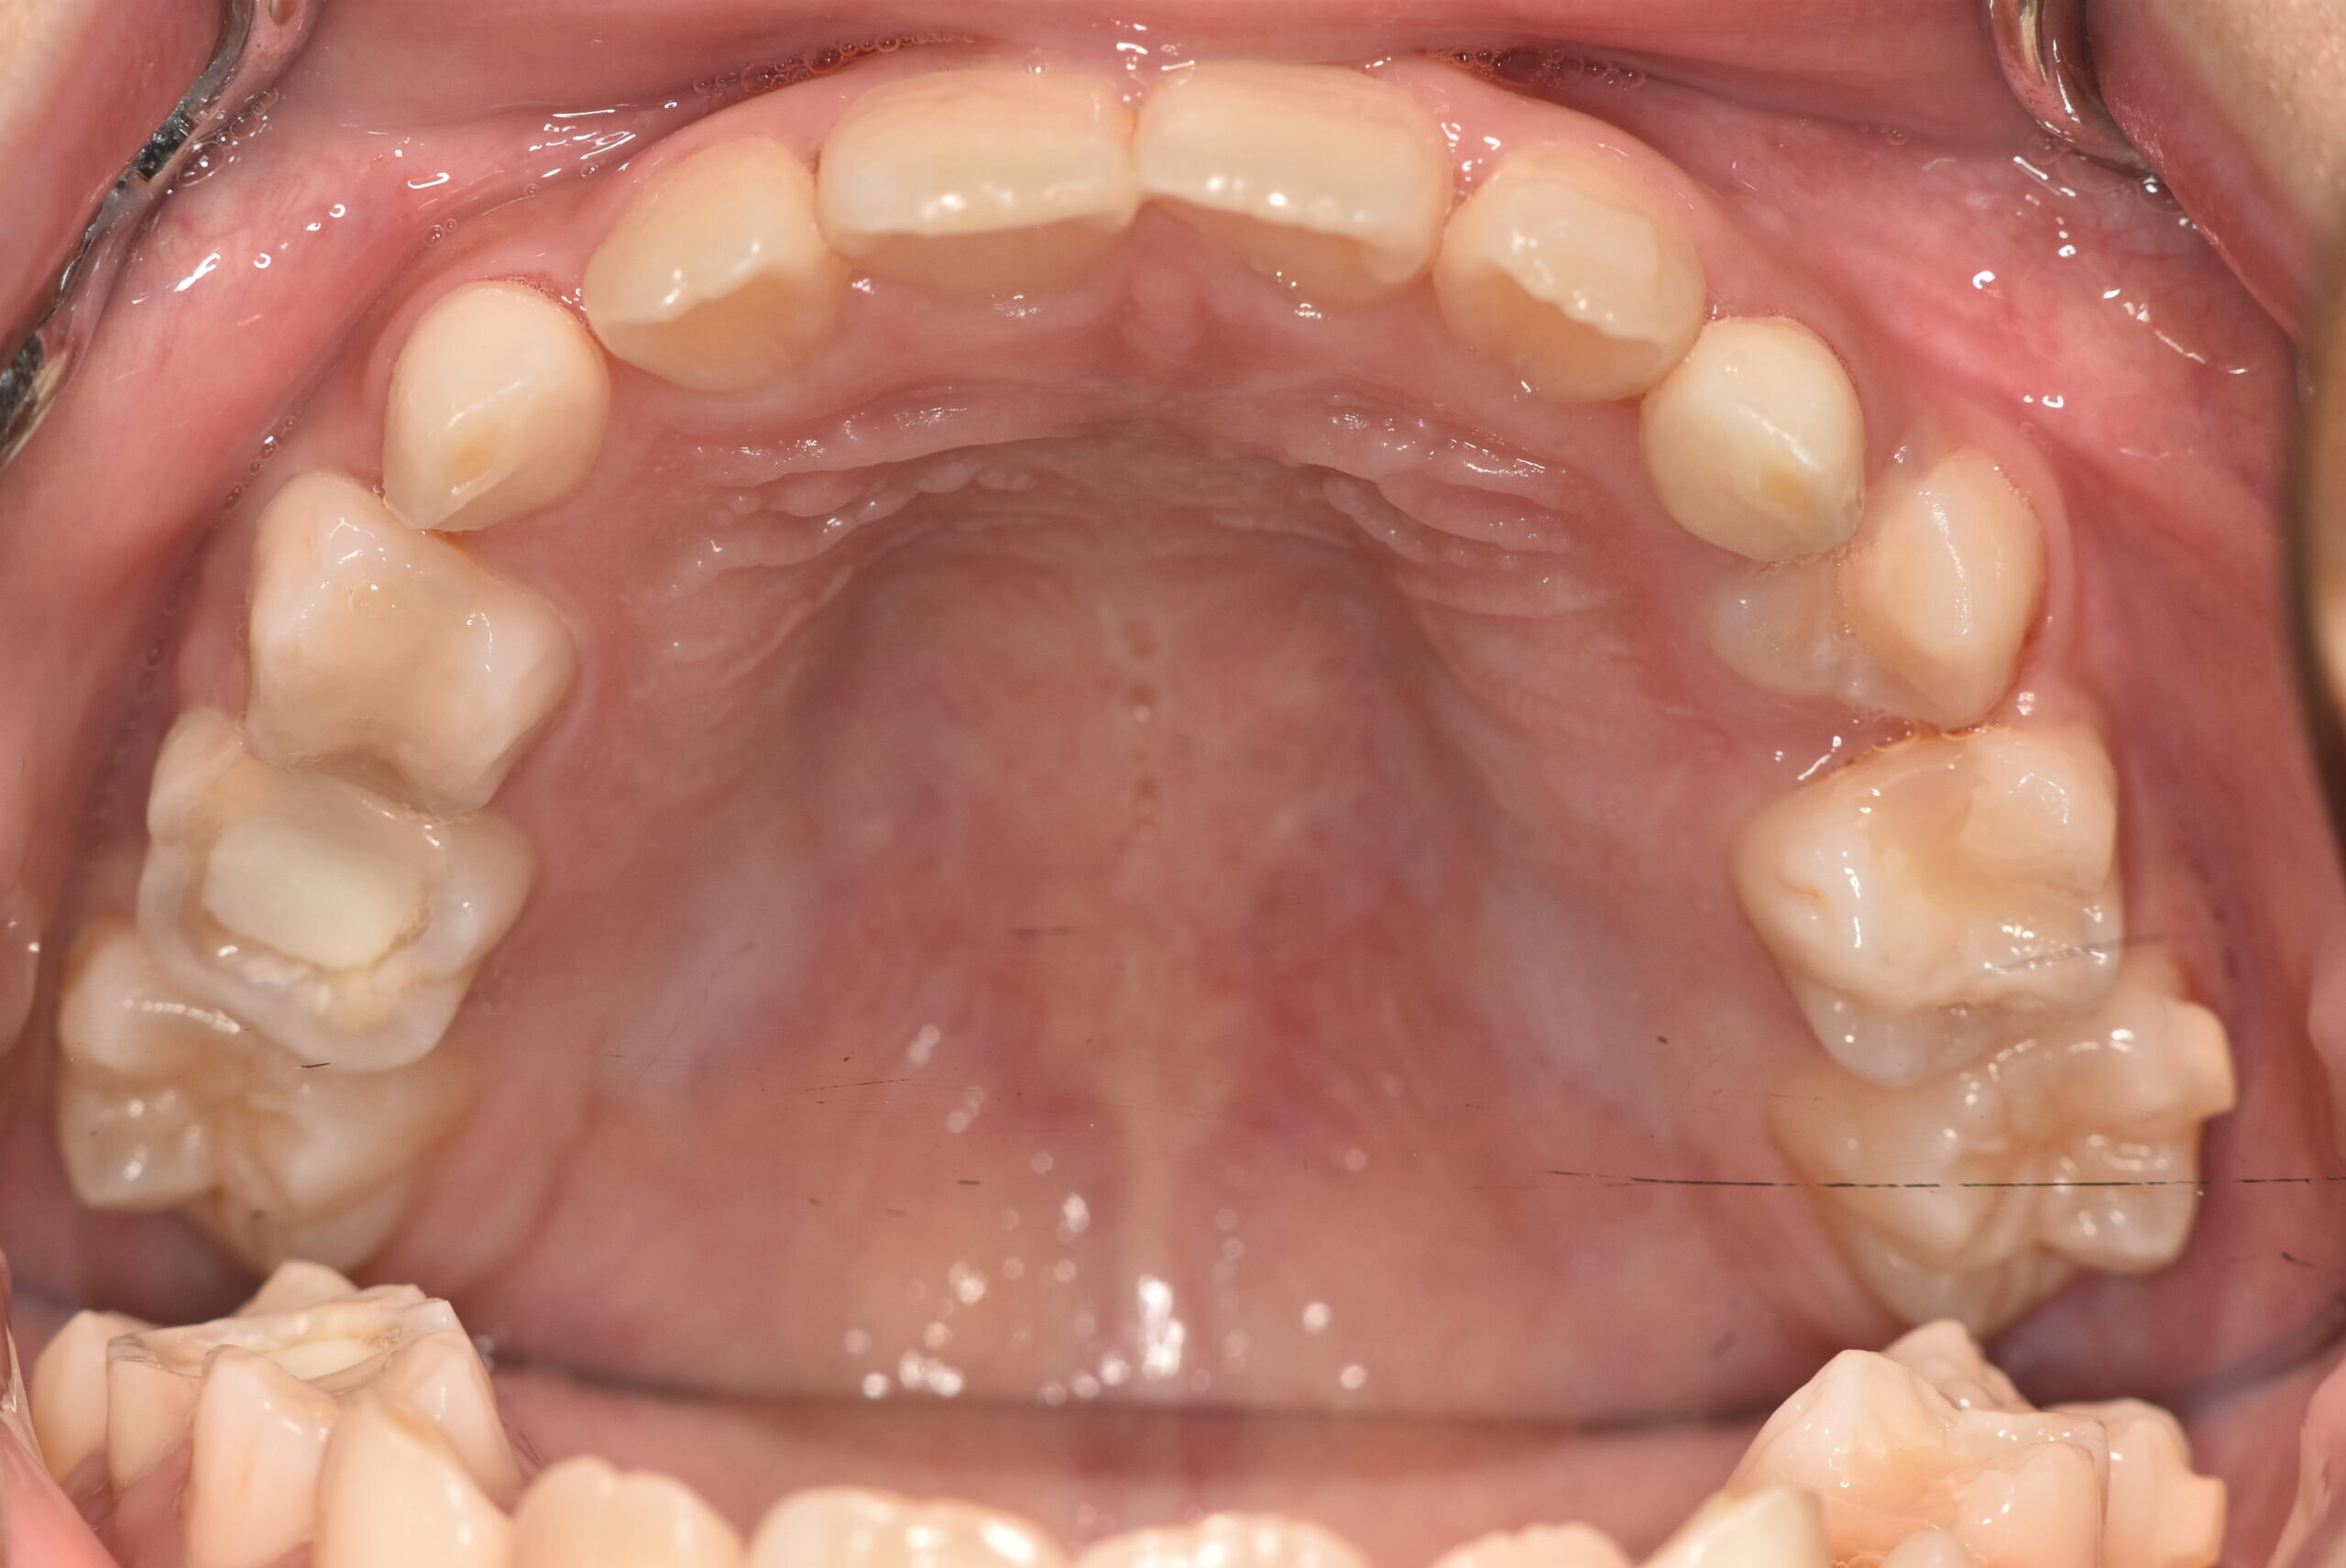

| 治療内容の詳細 | 初診時9歳3ヶ月の男児で、前歯が磨きにくく虫歯になりやすいことを気にされ来院されました。 検査の結果、前歯部叢生を伴うアングルⅠ級不正咬合と診断しました。 治療としてはマウスピース矯正(インビザラインファースト)で配列を行い、上下顎の側方拡大により永久歯の萌出スペースを確保しました。 治療期間は、1年6ヶ月でした。 今後、永久歯(側方歯)の生え変わりまで経過観察を行います。 |